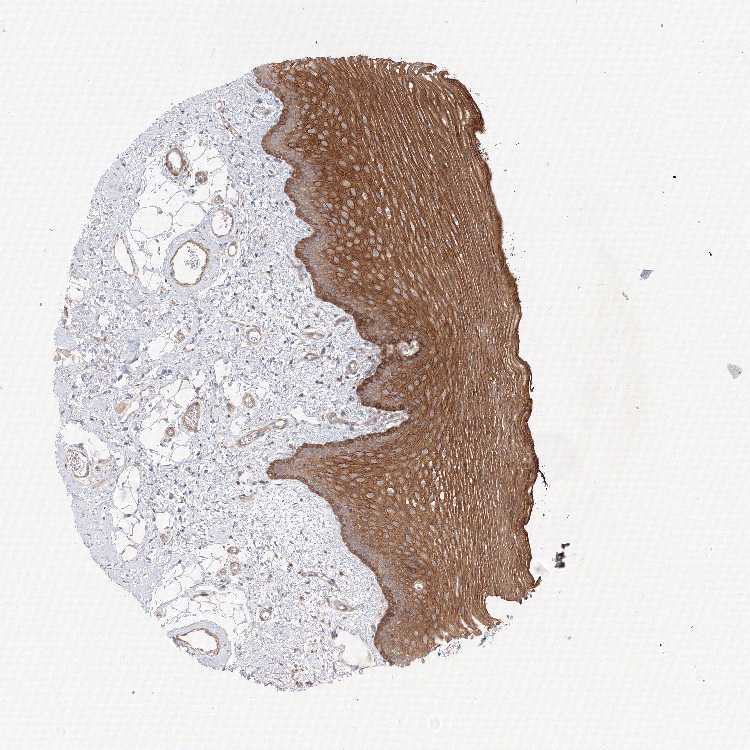

TISSUE PRIMARY DATA ORAL MUCOSA Show tissue menu

Oral mucosa

ORAL MUCOSA - Antibody stainingi

Antibody staining in the annotated cell types in the current human tissue is reported as not detected, low, medium, or high, based on conventional immunohistochemistry profiling in selected tissues. This score is based on the combination of the staining intensity and fraction of stained cells.

Each image is clickable and will lead to virtual microscopy that enables deeper exploration of all samples and also displays staining intensity scores, fraction scores and subcellular localization as well as patient and tissue information for each sample.

Antibody HPA037922Antibody HPA037923

Squamous epithelial cells MediumHigh